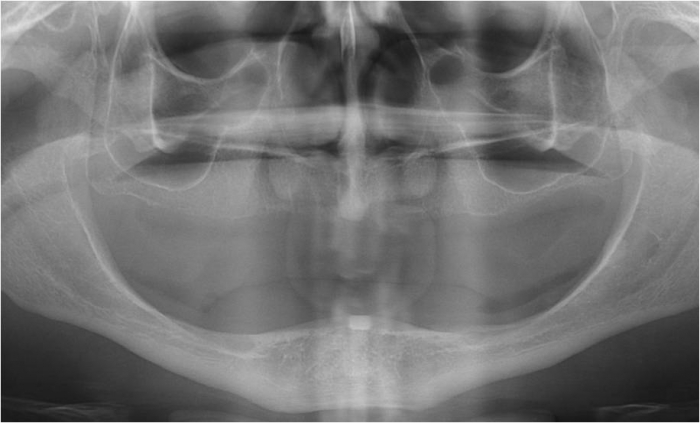

Raio x inicial